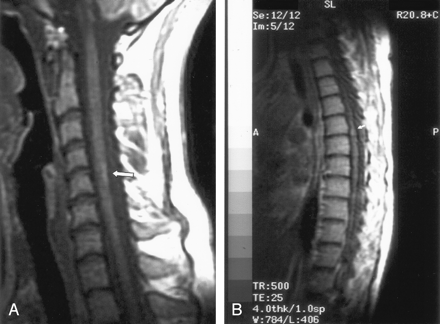

On the dermatologic examination, diffuse asymptomatic papules were found, mostly in the lower limbs. These lesions had a diameter of a few millimeters, were surrounded by a erythematous rim, and their color was pink, with a central atrophic area characterized by adherent whitish desquamation (Fig 1); a skin biopsy on the leg confirmed the diagnosis of Degos disease (Fig 2). The neurologic examination noted anisocoria, hearing loss on the left side, diffuse muscle hypotrophy, impaired finger movements, mild paresis of the right arm, paralysis of both legs, symmetrically reduced muscular reflexes, hypoesthesia, hypopallesthesia of the lower limbs, constipation, and urinary incontinence. No fever or meningeal signs were present. Brain MR imaging (Figs 3–5) showed both old and new ischemic lesions, mainly present in the left hemisphere, and numerous small nodules, localized in both the cerebral and the cerebellar cortices. A diffuse and homogeneous thickening of the meninges, with some subdural fluid accumulation, was also evident in the frontoparietal region. Ependymal enhancement was noted in the atrium of the right lateral ventricle. Hydrocephalus and venous thromboses were ruled out. Spinal MR imaging showed thinning of the spinal cord, with mild alteration of the signal intensity in the thoracic cord (Fig 6). A subtle, focal cord enhancement was found in the cervical and thoracic cord (Fig 7).

In our patient, the most important radiologic aspect was the presence of disseminated small cortical nodules, expression of superficial vasculitis, and leptomeningeal fibroinflammatory deposits. The signs of ependymitis we found in the right lateral ventricle (Figs 3 and 4) seem to indicate that inflammatory phenomena were superimposed to the vascular damage, as already described in some forms of Degos diseases with a meningoencephalitislike presentation (15). In addition, the dural thickening, in the absence of venous thrombosis, is compatible with the hypothesis of a superimposed inflammatory process and represents a chronic fibroinflammatory finding. The presence of a small subdural fluid collection should be the result of a CSF equivalent effusion or of blocked CSF spaces rather than a chronic subdural hematoma (Figs 4 and 5). Finally, the involvement of the spinal cord was confirmed by the history and the clinical findings of our patient; we noted, beyond a global reduction in the spinal cord thickness, the presence of focal abnormalities in cervical and thoracic cord (Figs 6 and 7).

T1 (contrast-enhanced) sagittal images show subtle cord enhancement in the dorsal cervical region and at midthoracic level (arrows).